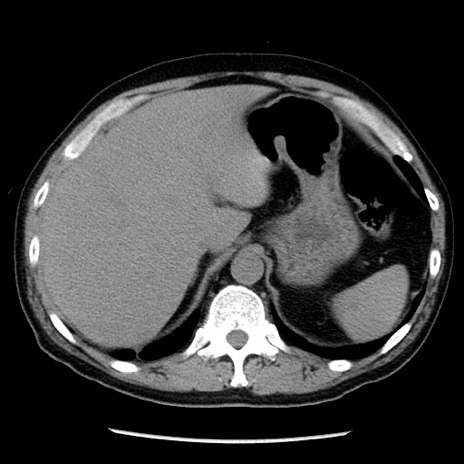

冠状断像

【症例】40歳代男性

【現病歴】2日前から胃痛あり。徐々に周期的な激痛に変化した。本日になっても激痛があるため受診。

【身体所見】意識清明、BT 38-39℃台あり、腹部:膨満、やや硬、右下腹部に圧痛あり。

【データ】WBC 8500、CRP 23.26